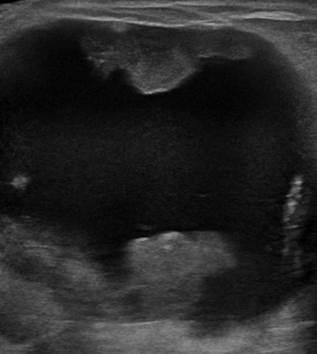

Ung thư vú

Ung thư vú - Ảnh 4

» Thông tin: Nữ giới – 85 tuổi.

» Lâm sàng: Khối tuyến vú.